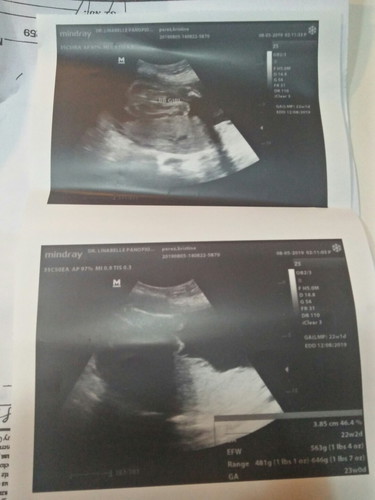

Its a girl❤?.... Hehe... Natuwa lng aq dahil un expect q and eto nga.. Girl xa.. Hehe..... Nweiz hello to all momshies?❤ God bless po?

22 weeks po😊

22 weeks mommy😊